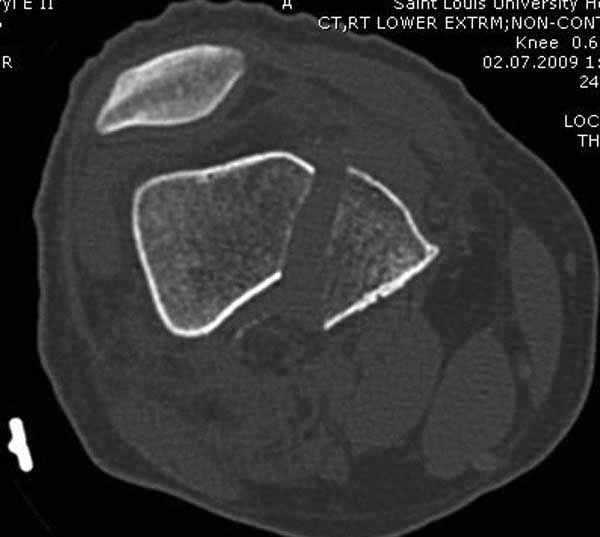

И не обратите, коллега, пока не сделаете четкие анфасные снимки (лучше с дистракцией) где будет четко визуализироваться малоберцовая кость. Думается, что и КТ здесь будет уместно, дабы не пропустить возможное флексионное повреждение (перелом Hoffa).

А теперь по поводу лечения перелома. Среди всех чрез/меж-мыщелковых переломов в 38% сопровождются переломом в корональной плоскости, т.е перелом Hoffa. Nork et al, J Orthop Trauma, 87:564, 2005.

У больных как в этом случае, с вовлечением двух мыщелков правильно, что сделали вытяжение до операции. Здесь имеется флексионный компонент на другой стороне, и я бы рекомендовал операцию делать из двух доступов. Сперва фиксировать медиальную колонну custom made пластиной, обычно 1/3 тубулярной пластиной в 4.5 мм, потому что пока производители опаздывают с медиальной пластиной.

Однако в случае, представленном Константином Никитиным, не может быть применён ни ретроградный ни антеградный остеосинтез. Причина - нереально выполнить вышеуказанные необходимые требования, касающиеся дистальных блокирующих винтов. Из-за низкого перелома латерального мыщелка (перелом Hoffa) невозможно через него провести хотя бы 2 блокирующих винта, поскольку линия перелома мыщелка расположена либо на уровне верхушки межмыщелковой ямки либо незначительно проксимальнее. Поэтому авторам, с моей точки зрения, необходимо прислушаться к рекомендациям Джолдаса.

Рационально ориентироваться на качественный аспект - проблема или решается, или нет. Переломы типа 33C1 или C2 (то есть без фронтального раскалывания мыщелков, как на показанной Вами томограмме) при обычном качестве кости успешно можно фиксировать гвоздями с фронтальными винтами. Получается, их прочностных характеристик уже достаточно.